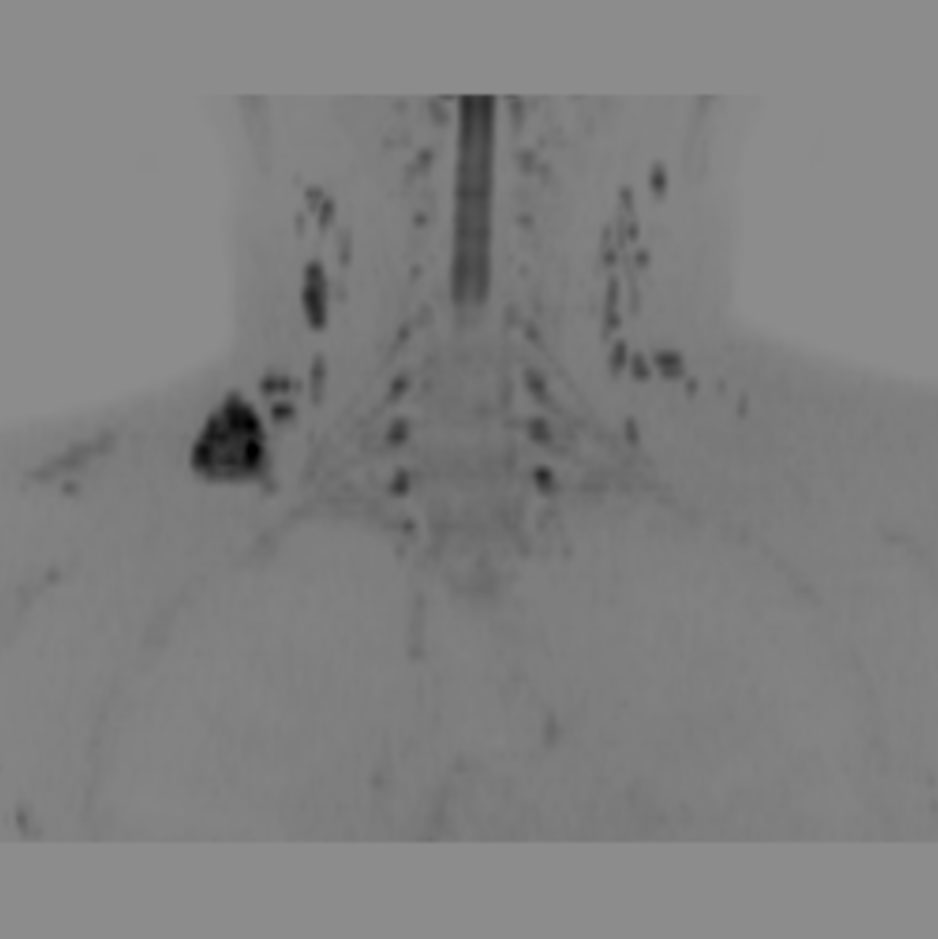

Coronal DWIBS (MIP)